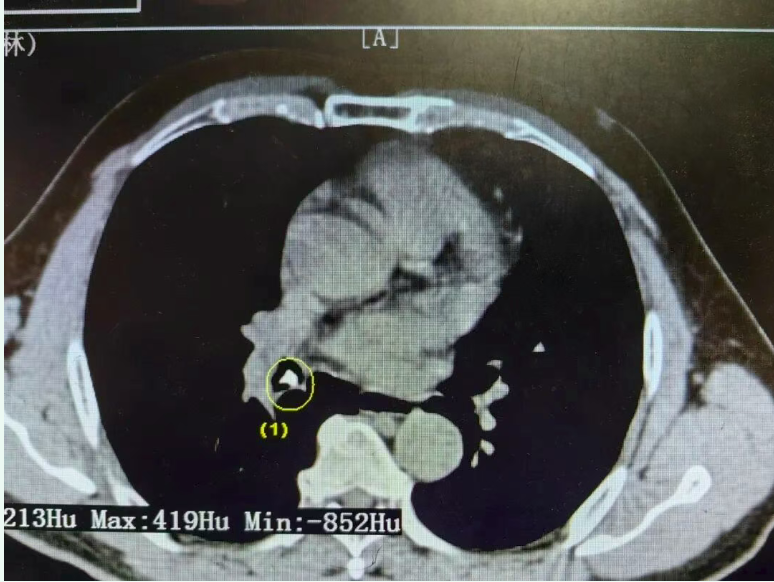

本以为只是普通呛到了,没想到接下来的几天,咳嗽越来越重,尤其到晚上根本没法平躺睡觉,后来甚至还咳出了鲜血。9月11日,郑大爷到浮梁县人民医院做了CT,结果显示右肺支气管有阴影,起初还怀疑是肿瘤,一家人顿时紧张起来。

当天中午12:00,依托医联体建设,他们立即就转至景德镇市第一人民医院,找到了呼吸与危重症医学科的副主任医师郑巍亮。详细问诊和重新阅片后,郑医师判断:“这不像肿瘤,更像是支气管被异物堵住了!”此时郑大爷仍然咳嗽剧烈、间断咯血,情况紧急。主任卢志军、医生郑巍亮快速完成术前准备,联合麻醉科,在无痛支气管镜下迅速探查——果然,在右肺中间段远端发现了一块骨性异物,尖端已扎入支气管黏膜,周围还有出血。